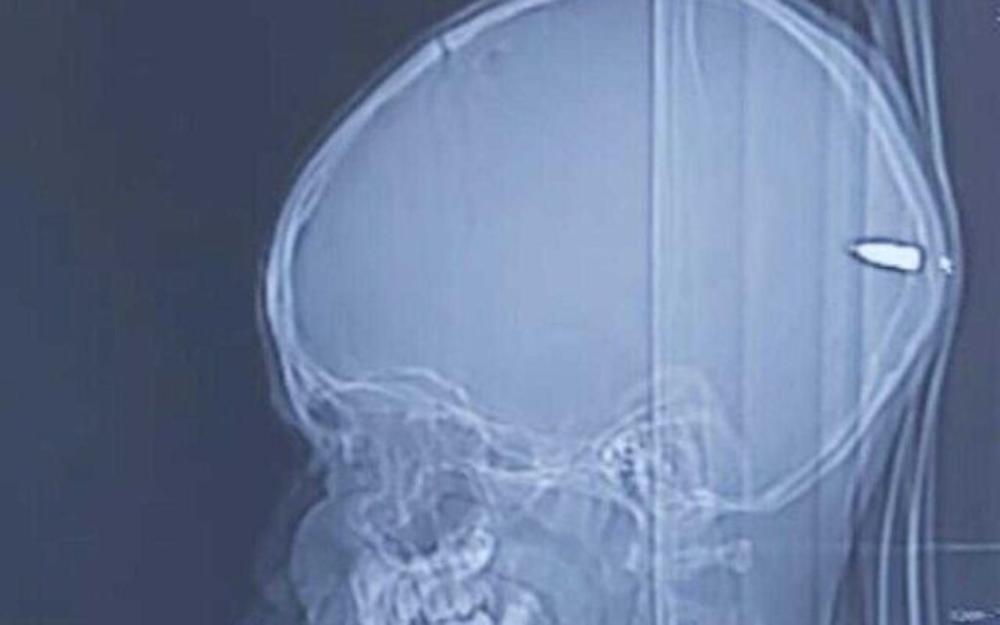

Doktori su ga odmah pregledali, a na glavi su mu pronašli malu ranu i krv. Odmah su uradili skener nakon čega su otkrili kako dečak ima metak u glavi. Metak je prošao kroz lobanju i zaustavio se u dečakovom mozgu.

Neurohirurg Gaj Elor, koji je izvadio metak iz dečakove glave, kaže da roditelji nisu znali da je njihov sin pogođen.

"Da je metak otišao u drugom smeru, mogao je da prouzrokuje mnogo veću štetu i značajno neurološko oštećenje", rekao je lekar i dodao da se dečak dobro oporavlja i razgovara sa svojom porodicom.